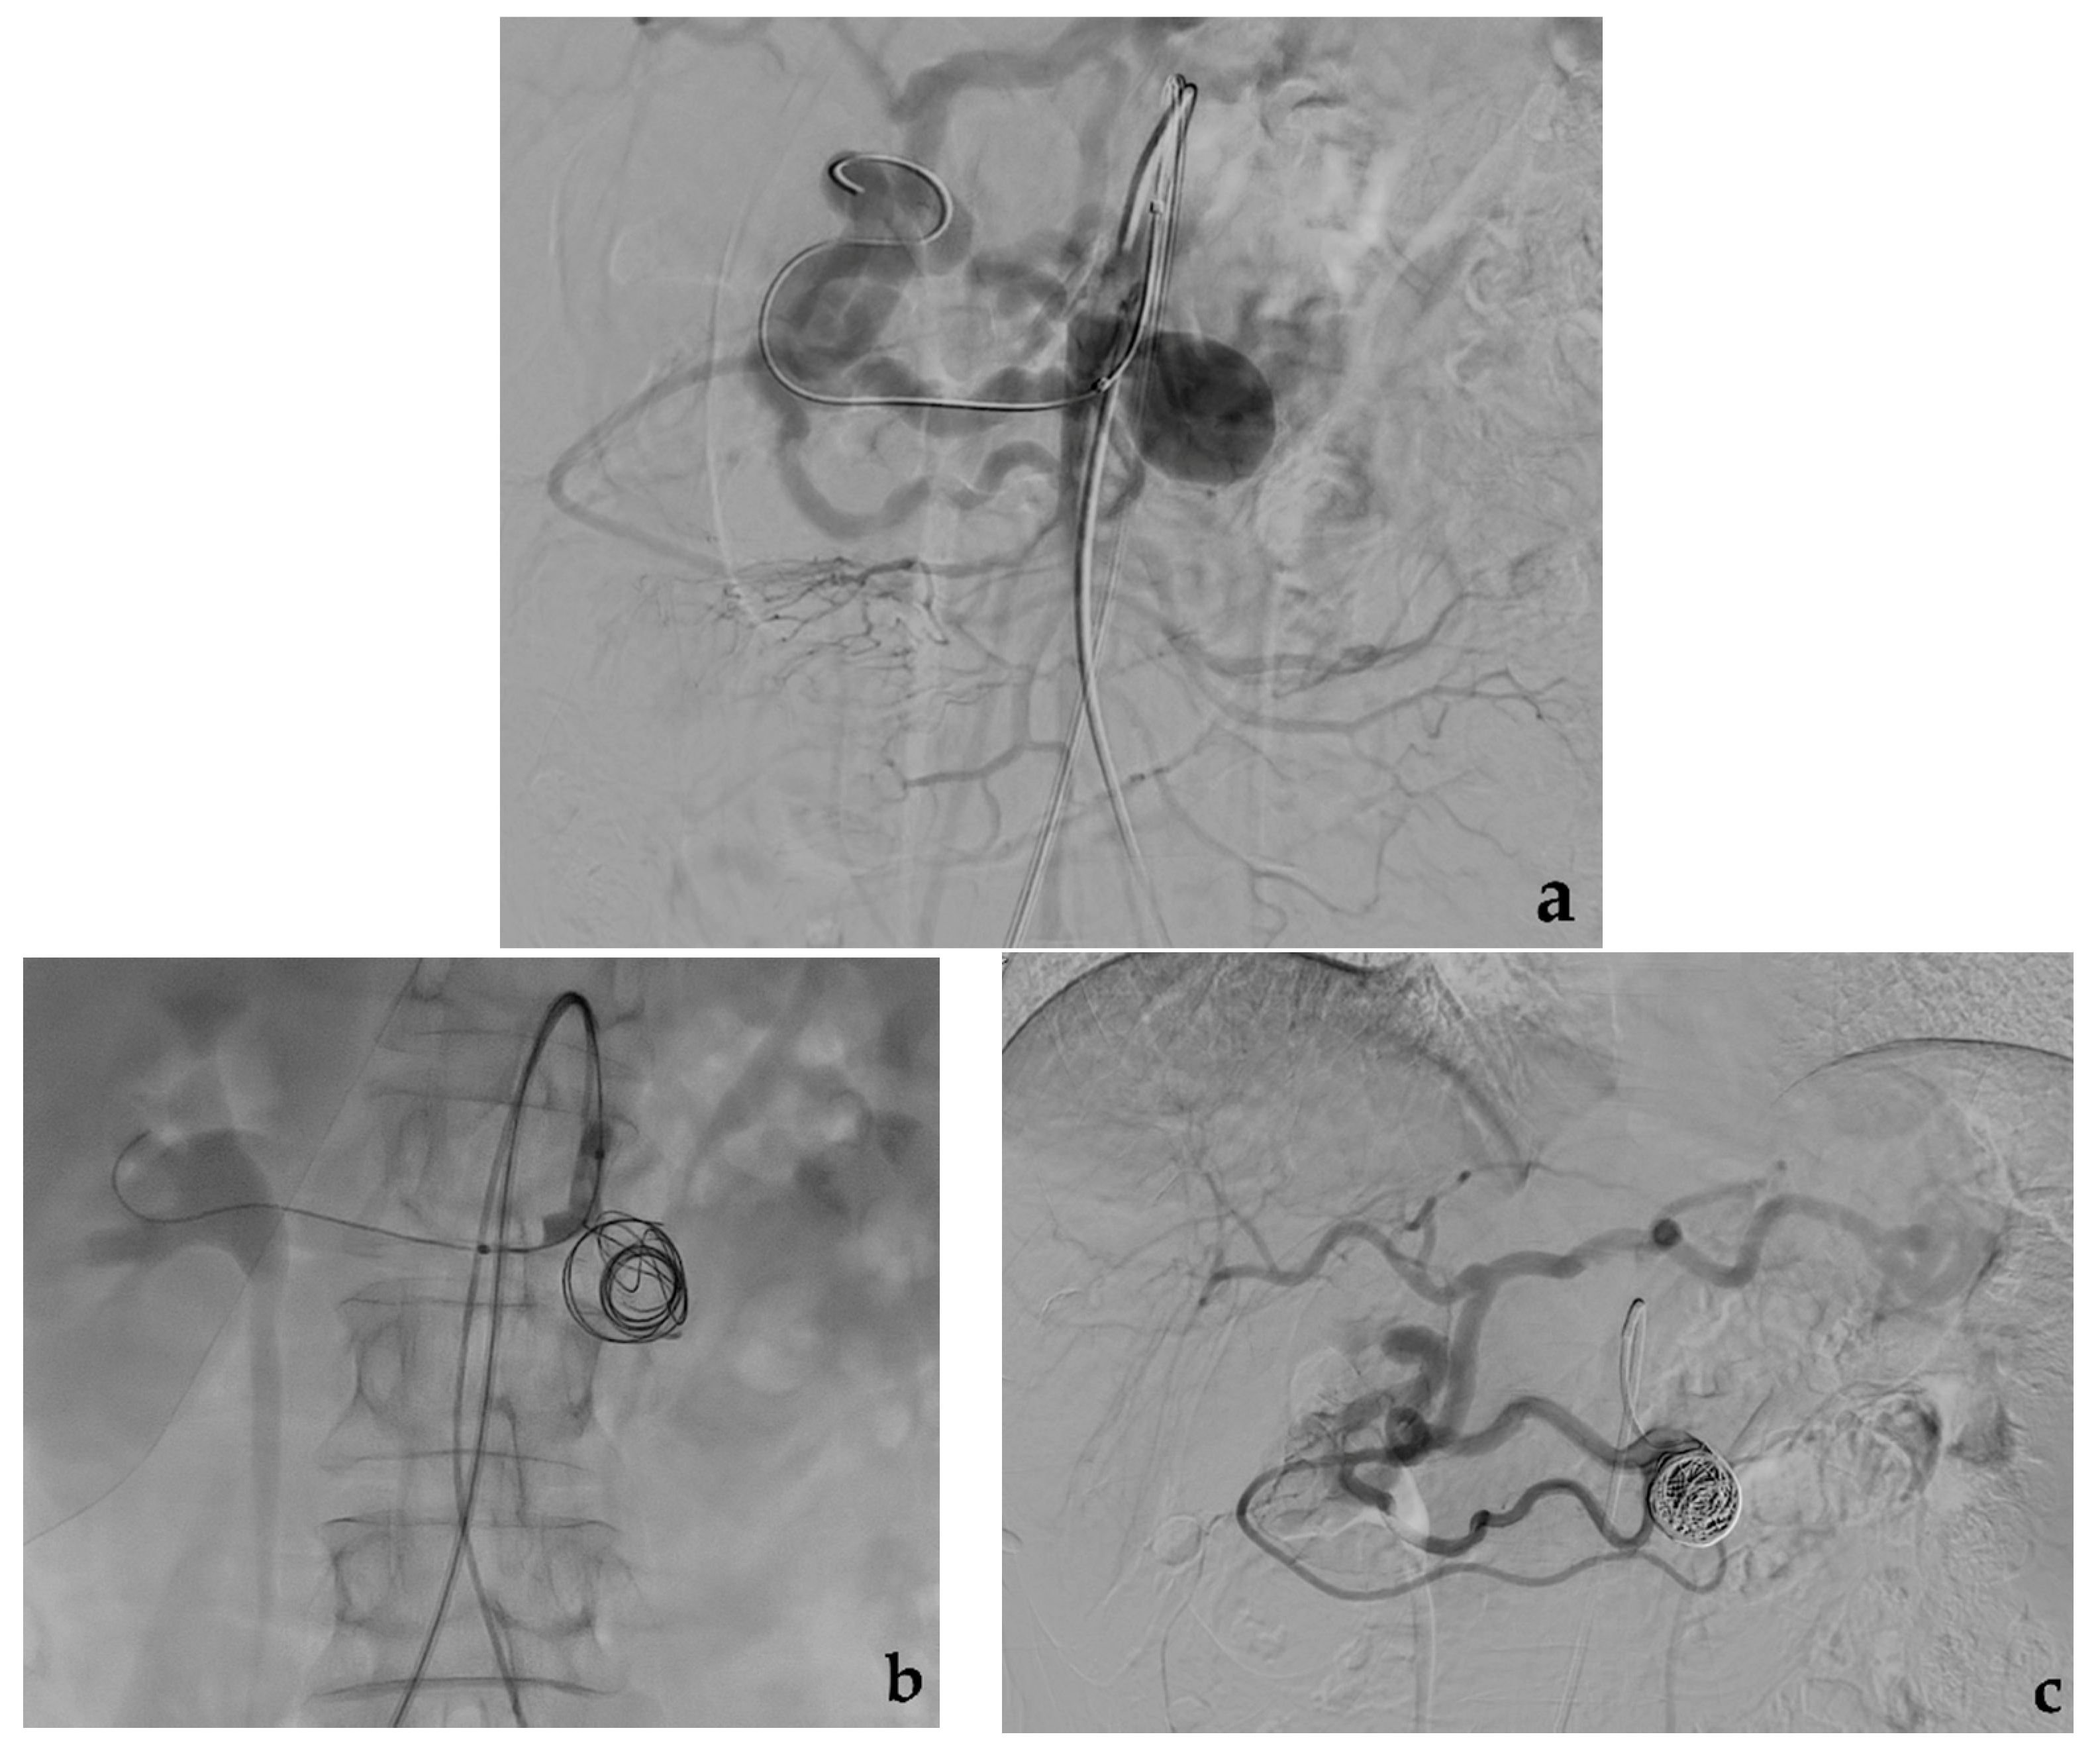

3.1. Coil Embolization

- Modestino, F.; Cappelli, A.; Mosconi, C.; Peta, G.; Bruno, A.; Vara, G.; De Benedictis, C.; Golfieri, R. Balloon-assisted coil embolization of a wide-necked aneurysm of the inferior pancraticoduodenal artery. CVIR Endovasc. 2020, 3, 62. [Google Scholar] [CrossRef] [PubMed]